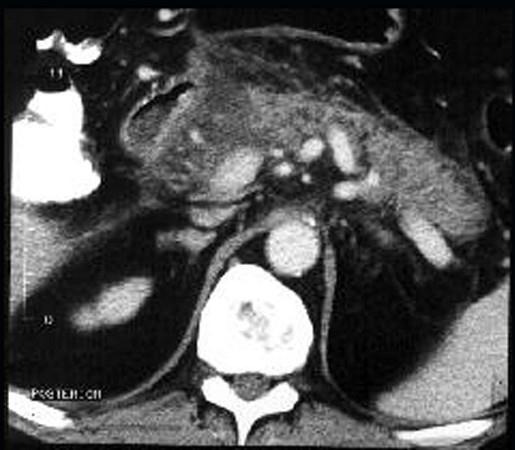

问题 男,32岁,上腹部持续性疼痛,放射至胸背部,高热,恶心呕吐,上腹部压痛反跳痛,CT检查如图,最佳的诊断是 ( )

选项 A、慢性胰腺炎急性发作 B、胰腺癌 C、出血坏死性胰腺炎 D、慢性胰腺炎 E、急性单纯性胰腺炎

答案 C